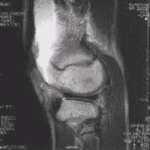

معرض الصور